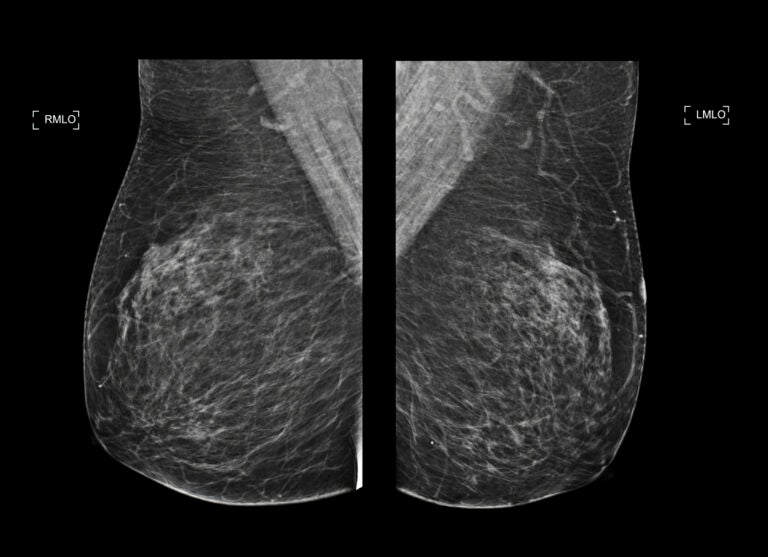

Health professionals in Pennsylvania are expanding the use of mammograms beyond breast cancer screening to detect early signs of heart disease in women. This innovative approach focuses on identifying calcium buildup in the blood vessels of the breast, known as breast arterial calcification (BAC), which can indicate an increased risk of cardiovascular issues.

Calcium buildup in arterial walls has long been recognized as a precursor to cardiovascular disease. Medical professionals typically assess heart disease risk through coronary artery calcium scans, a noninvasive imaging technique. However, as Nudy pointed out, mammograms can also reveal calcium deposits in breast blood vessels, which may contribute to stiffer and narrower vessels—both indicators of heart disease.

Radiologists review every mammogram for evidence of BAC and inform patients accordingly. This proactive approach allows doctors to connect women with specialists for further heart health evaluations. Jefferson Health, in collaboration with Solis Mammography, has also launched the Mammo+Heart program, which employs artificial intelligence to analyze BAC in mammogram images more comprehensively. This optional service incurs an additional cost but offers deeper insights into heart health.